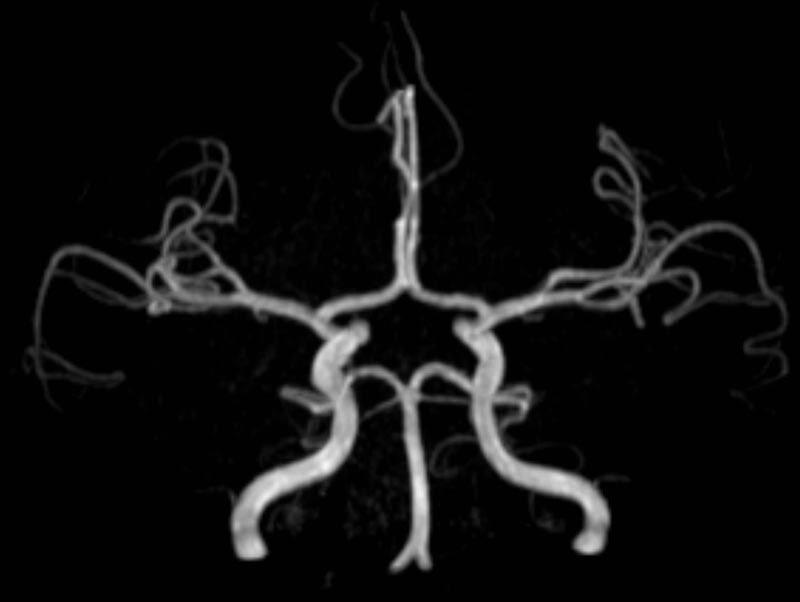

• intrakranielle Gefäße (Abklärung Verschluss, Stenose, Aneurysma)

MR-Angiografie (MRA)

Angiographie ohne Kontrastmittel

• MR-Angiografie ohne Kontrastmittel

• Time of Flight (TOF)-Angiographie

• Phasenkontrastangiographie (PCA). Geeignet zur Quantifizierung Stenose-/Insuffizienzgrad z.B. bei Herzklappen, falls echokardiographisch die Untersuchungsbedingungen eingeschränkt sind.

Je nach Fragestellung und Körperregion Gefäßdarstellung ohne Kontrastmittel bei Kontrastmittelunverträglichkeit oder terminaler Niereninsuffizienz möglich.

Ganzkörper Angiographie mit Kontrastmittel

• MR-Angiographie mit Kontrastmittel

• Erfassung arterieller und venöser Gefäße/Bypässe aller Körperregionen mit 3D-Rekonstruktion

• je nach klinischer Fragestellung zeitaufgelöste MR-Angiographie (4D-MRA) z.B. bei Frage arteriovenöse Fistel/ Shunt oder Darstellung Unterschenkelarterien vor geplanter Bypassoperation.